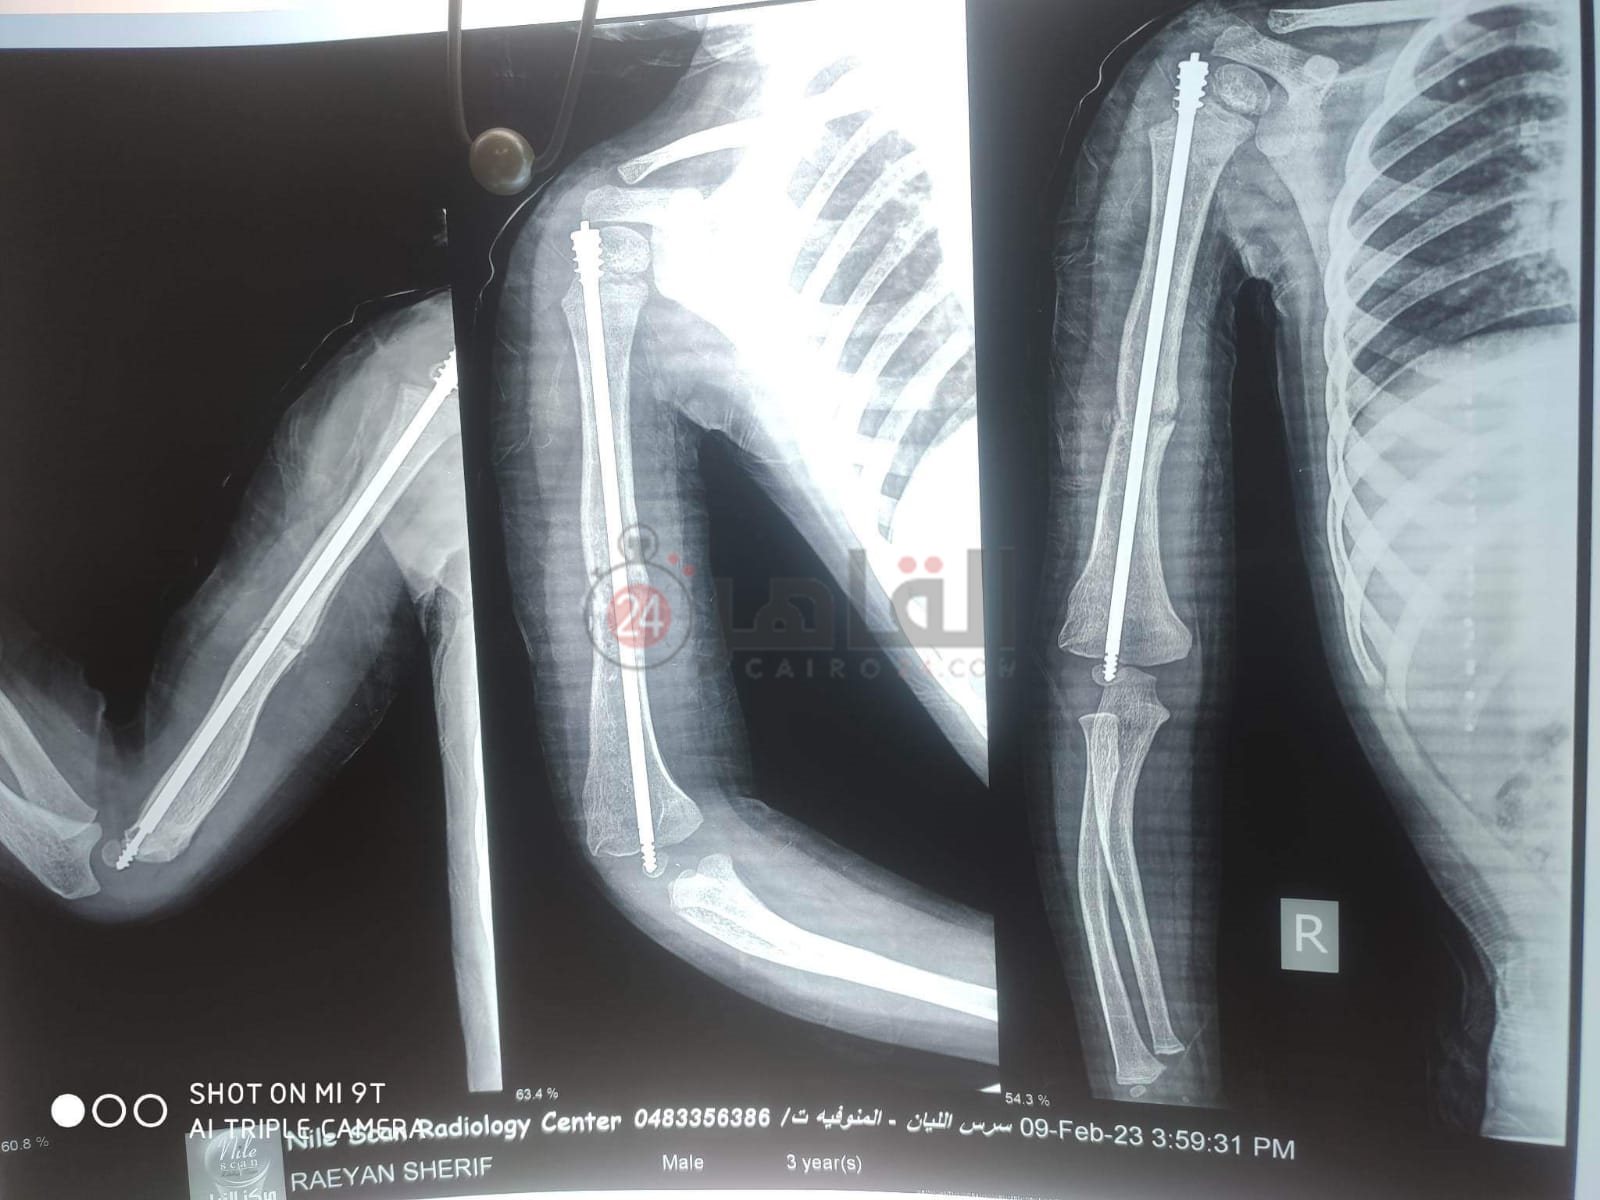

ريان طفل بالمنوفية يعاني من مرض العظم الزجاجي والذي يجعله عرضه لكسر العظام بشكل متكرر، صاحب الثلاث سنوات ونصف تعرض للكسر ما يزيد عن 51 مرة، في كل أطراف الجسم بالإضافة إلى خضوعه لعملية جراحية لتركيب مسمار مطاطي نخاعي في الذراع الأيمن ويحتاج لعملية جراحية أخرى لتركيب نفس المسمار في الذراع الأيسر خلال 15 يوما على الأكثر.

وتروي والدة ريان لـ القاهرة 24 مأساة ابنها صاحب الثلاث سنوات ونصف، والذي يتعرض للكسور بشكل متواصل، وتؤكد على حجم المعاناة التي تعرض لها الصغير حيث تعرض ذراعه الأيمن لـ 21 كسرا، والذراع الأيسر 18 كسرا وكل قدم من أقدامه 6 كسور بالإضافة إلى تجبيس كامل في القدمين بـ 5 بناطيل من الجبس.

وتؤكد والدة الطفل والذي يقيم بمدينة سرس الليان، أن والده يعمل صنايعي بأحد المحلات، وابنها يحتاج حقنة بـ 2500 جنيه شهريا، وخضع لعملية جراحية لتركيب مسمار مطاطي نخاعي في الذراع الأيمن بمبلغ 65 ألف جنيه ويحتاج لأخرى في اليد اليسرى بمبلغ 75 ألف جنيها وهي خارج إمكانية الأسرة في الوقت الحالي، وتناشد المسئولين التكفل بحالته التي تحتاج إلى استشاري عظام كبير حتى يتمكن من تركيب المسمار بشكل صحيح، حيث أن تلك العملية تحتاج لبراعة وخبرة.